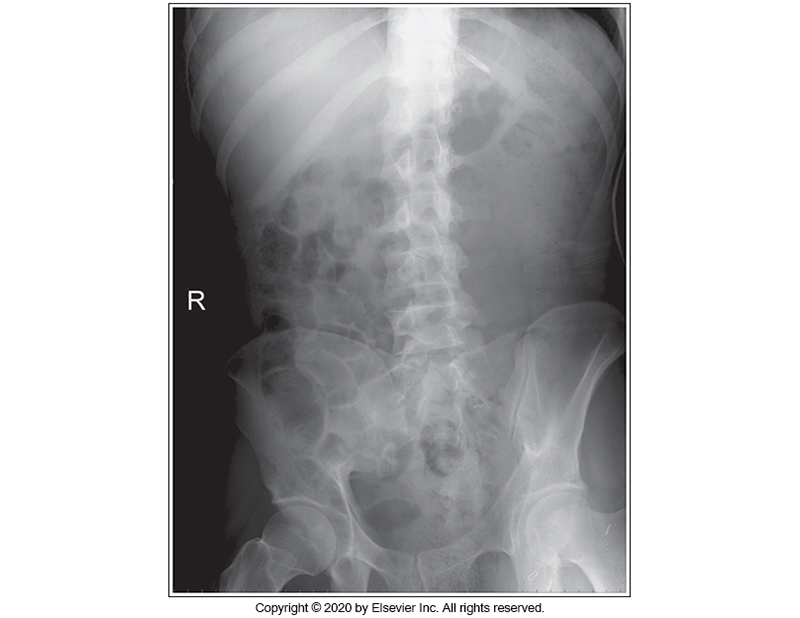

Identify the main problem of the image below (AP Supine abdomen)

The image is taken on full inspiration.

The MCP is tilted anteriorly.

Patient is in an LPO position.

Patient is in an RPO position.